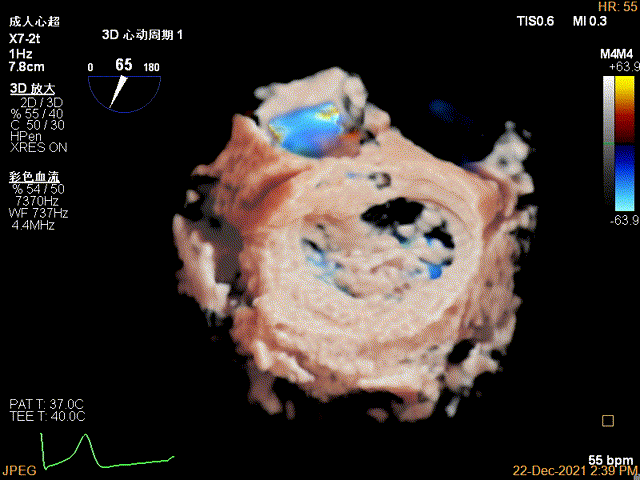

3D-color-VIEW验证残余分流,位于第一个夹子外侧

决定在外侧补放第二个夹子,沿着大鞘输送第二个夹子

3D-VIEW提示第二个夹子置于第一个夹子外侧,并呈平行关系

抓捕外侧残余脱垂瓣叶

夹子闭合中,残余分流逐渐消失

第二个夹子放置侯二尖瓣口平均跨瓣压差:4mmHg

肺静脉血流频谱完全恢复正向

3D-VIEW验证抓捕结果

3D-color-VIEW验证残余分流近消失